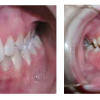

Ülemise hambakaare kitsenemine ehk tagumiste hammaste risthambumus

Hammustades on näha, et alumine hambakaar on laiem kui ülemine. Tagumine risthambumus võib olla kas mõlemapoolne või ühepoolne ja sageli hambakaarte keskjooned hammustades ei ühti. Tagumist risthambumust võib esineda 10...